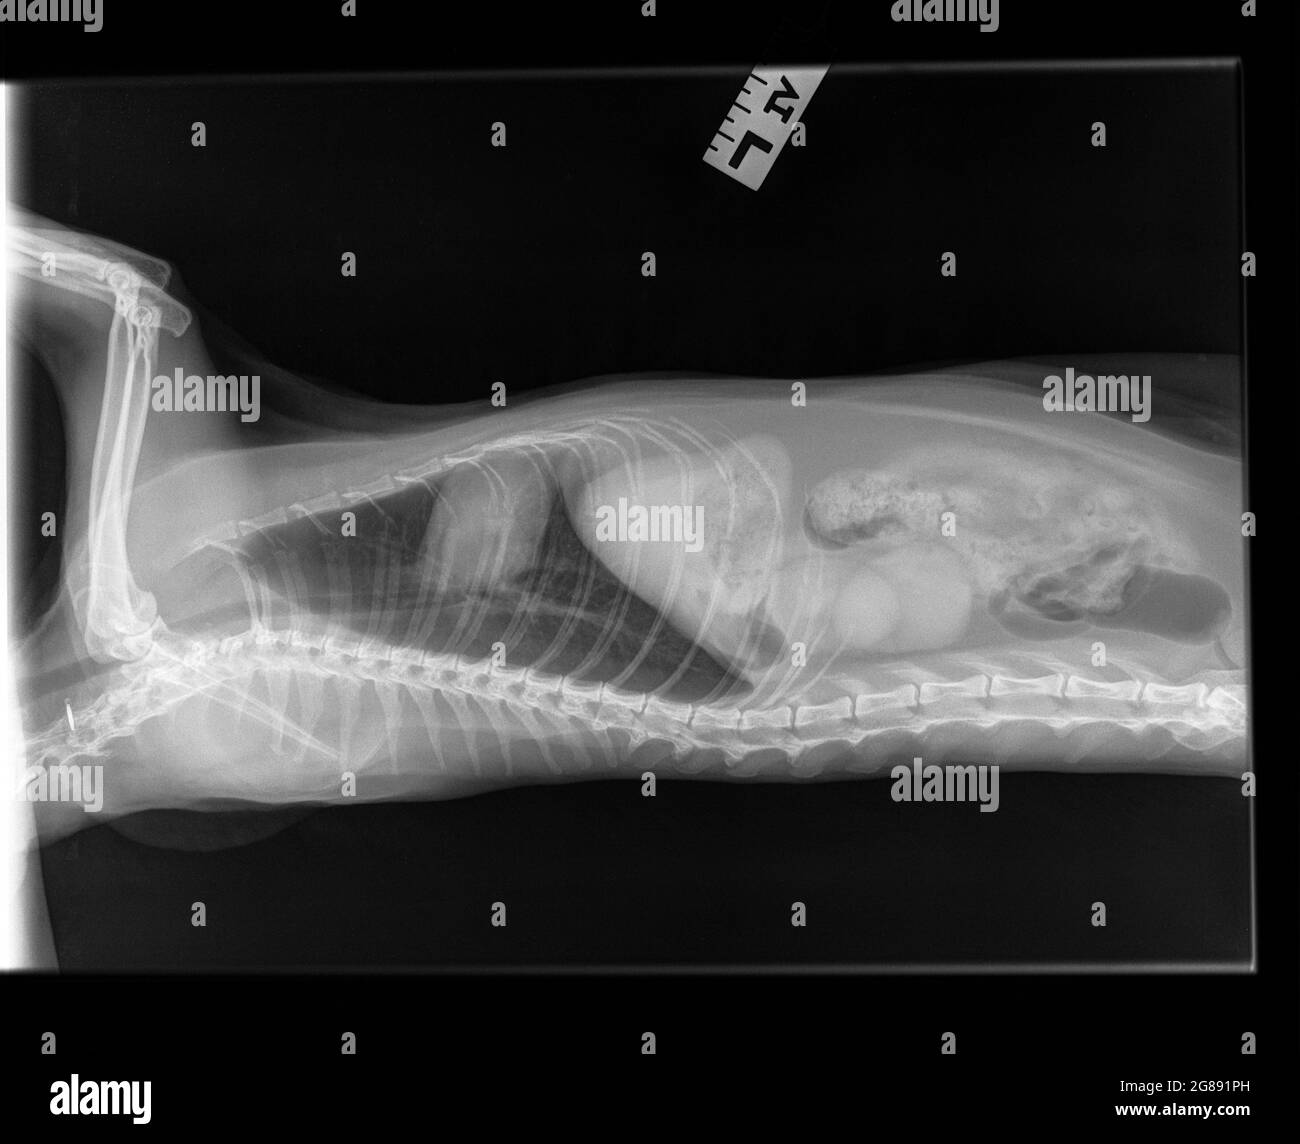

RF2G891PH–Radiographie d'un vieux chat femelle spayé. Vue latérale. Un chat suspecté d'être atteint d'une maladie rénale chronique (rénale). Une structure modifiée du rein gauche.